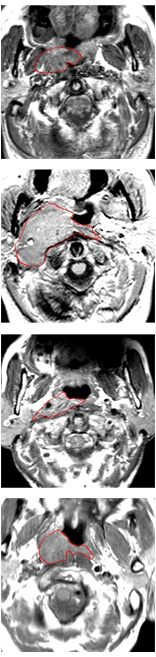

Currently, there is still no effort to fuse multi-modality MRI to develop an automatic segmentation system for NPC. According to researches of Popovtzer et al. [16], it should be a routine clinical practice to incorporate all kinds of MRI datasets in highly conformal radiation therapy to realize GTV delineation of NPC. For delineation of NPC, MRI is the perferred imaging modality for its superior soft tissue contrast [16, 3]. Moreover, MRI of different modalities data have different visual characteristics and various responses to different tissues and anatomical structures. For example, T1-weighted (T1) MRI is suitable for detecting skull base involvement and fat planes, while contrast-enhanced T1-weighted (CET1) MRI is used to identity tumor extent [3]. Figure 1 shows some examples of NPC response in T1, CET1 and T2-weighted (T2) MRI.

Comparison with ground truth. Some predicted results of MMFNet are shown in 2D images and 3D images in Figure 7 and Figure 8. As shown in these figures, although the shape and size of NPC are varied from each other, MMFNet can still accurately determine the regions of NPC and obtain the accurate contours of tumors. Through analyzing 2D images in figure 7, MMFNet has a capacity to fuse multi-modality MRI to reduce the confusion brought by intensity’ similarity between nearby tissues and NPC. The values of , and of MMFNet are shown in Table 1. MMFNet can reach the best results with , and .

Comparison with related works. Table 1 reports the values of , and for different methods. Predicted masks of different methods are illustrated in Figure 9 and Figure 10, which respectively present results in 2D and 3D images. Through comprehensively analyzing these results, the proposed MMFNet actually have the following properties: